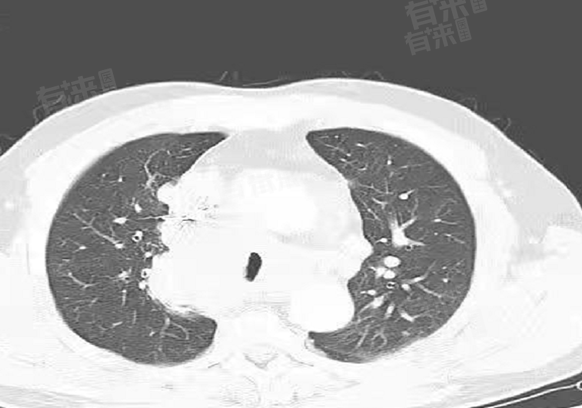

- 在影像学表现上,早期肺CA在胸部CT等检查中,可能呈现为小结节、磨玻璃影等特征,边界相对规整,与周围血管、支气管等结构关系不密切。这种相对清晰的影像特征有助于医生判断肿瘤的位置、大小,从而制定治疗方案。